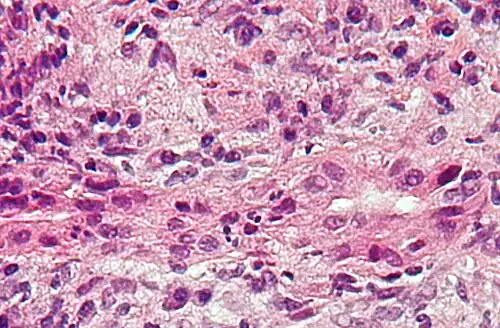

Micrograph of PBC showing bile duct inflammation and injury, H&E stain

On microscopic examination of liver biopsy specimens, PBC is characterized by chronic, nonsuppurative inflammation, which surrounds and destroys interlobular and septal bile ducts. These histopathologic findings in primary biliary cholangitis include:[32]

• Inflammation of the bile ducts, characterized by intraepithelial lymphocytes

• Periductal epithelioid granulomas.

• Proliferation of bile ductules

• Fibrosis (scarring)